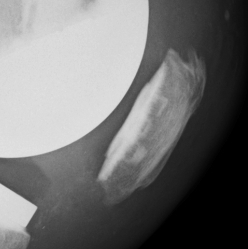

3. Patella fracture

- caused by excessive bone resection & holes in patella for fixation